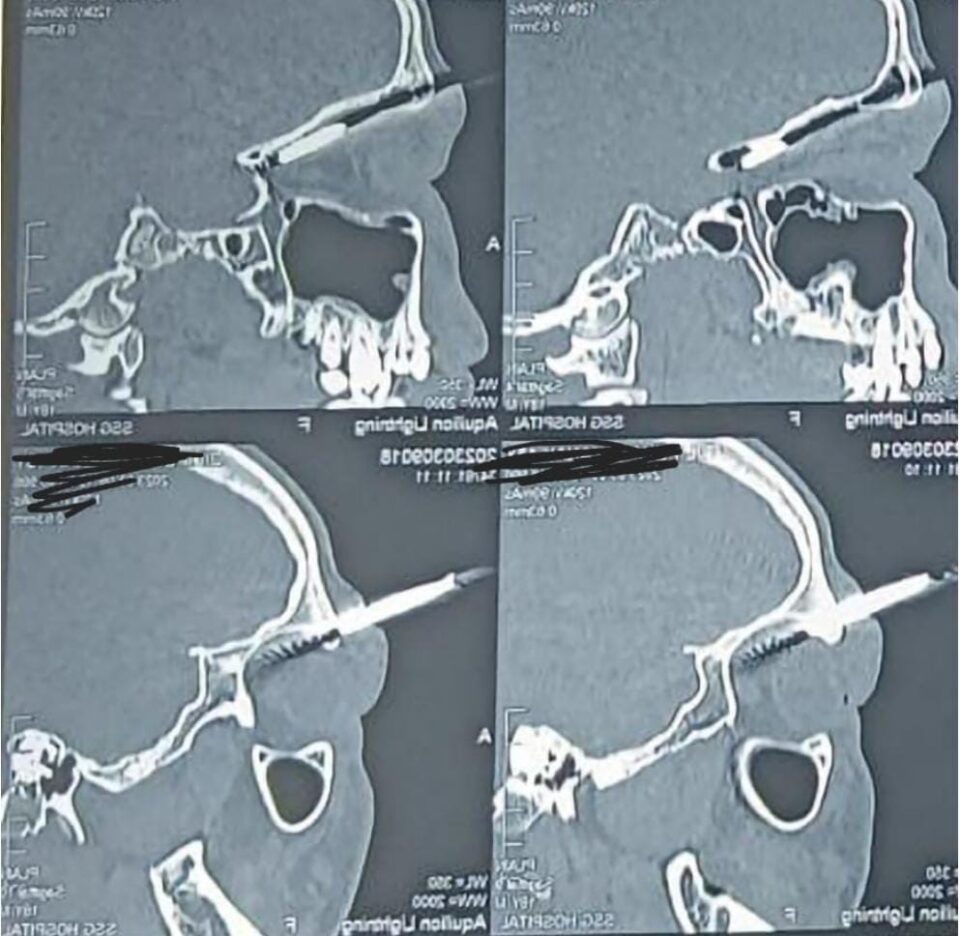

આ બનાવની વિગત મુજબ બે દિવસ પહેલા જ છોટાઉદેપુર જિલ્લાના ઉગલિયા ગામે દિલીપભાઇ ધામક પર તેમના પાડોશીએ તીર વડે હુમલો કર્યો હતો. તીરે તેની આંખને વીંધી, મગજમાં ઈજા પહોંચાડી હતી. તીરની ટોચ તેના મગજની મુખ્ય નળીઓની ખૂબ જ નજીક આવેલ હતી. ત્યારબાદ તેને તાત્કાલિક હોસ્પિટલ ખસેડવામાં આવ્યા હતા. જે જોઇને ડોક્ટર પણ આશ્ચર્યચકિત થઇ ગયા હતા અને ખૂબ જ પડકારજનક ઓપરેશન કરવામાં આવ્યુ હતુ.

ડૉ. પાર્થ મોદી, ડૉ. અંકિત શાહ, ડૉ. વિનય અને ડૉ. શ્રુતિબ જુનેજા આમ ન્યુરોસર્જન અને ઑપ્થાલોમોલોજિસ્ટની ટીમ દ્વારા તેમનું ઓપરેશન કરવામાં આવ્યું હતું,. લગભગ 3 કલાક ચાલેલી આ સર્જરી ખૂબ સફળ રહી હતી. જેમા તેની આંખ અને મગજની નળીઓ બંનેને બચાવવામાં આવી હતી. આ સફળ ઓપરેશન બાદ ડોક્ટર અને દિલીપભાઇના પરિવારજનોએ રાહતનો શ્વાસ લીધો હતો.